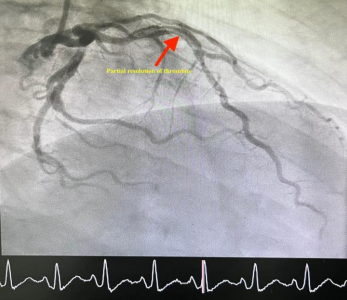

Coronary angiography showed a large caliber ectatic left anterior descending (LAD) artery, which was occluded by thrombus (Figure 1). Despite difficulties in wiring the LAD, the involved segment was successfully ballooned in an escalated fashion, restoring TIMI-3 flow. An ectatic segment that is just distal to the involved segment was also noted, which was studded with thrombus, resulting in a very hazy picture (Figure 2). Although attempts were made to aspirate the thrombus using an Export catheter (Medtronic, MN, USA), it was unsuccessful. Since the patient was symptomatically and hemodynamically stable, a decision was then made to medically manage him for the next 24-48 hours before attempting the procedure again.

Figure 1: Diagnostic angiogram showing a complete occlusion of LAD.

Figure 2. Baseline Coronary Angiography showing large thrombotic lesion in the LAD (arrows)